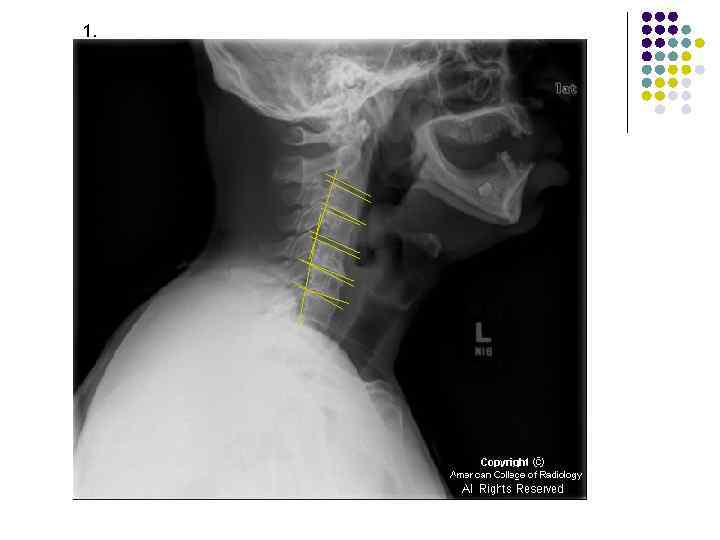

1.

l l l На рентгенограмме шейного отдела позвоночного столба в боковой проекции определяется: выраженные дистрофические изменения за счет остеохондроза - значительное, неравномерное сужение межпозвонковых пространств с нарушением их правильной клиновидной формы, выраженный субхондральный остеосклероз, значительные костные разрастания по передним краям тел позвонков. Наиболее ярко эти изменения представлены в сегментах С-5, 6, 7. Помимо этого, в этих же сегментах фиксируются дистрофические изменения дугоотростчатых суставов – сужение рентгеновских суставных щелей, субхондральный остеосклероз и костные разрастания по краям суставных поверхностей. Выпрямление физиологического лордоза. Признаки системного нарушения статики тел позвонков в виде симптомов кифотической установки. Деструктивных изменений нет Заключение: Комплекс дистрофических изменений шейного отдела позвоночного столба в виде остеохондроза и артроза дугоотростчатых суставов с преимущественными проявлениями в нижних сегментах отдела. Нарушение статики тел позвонков